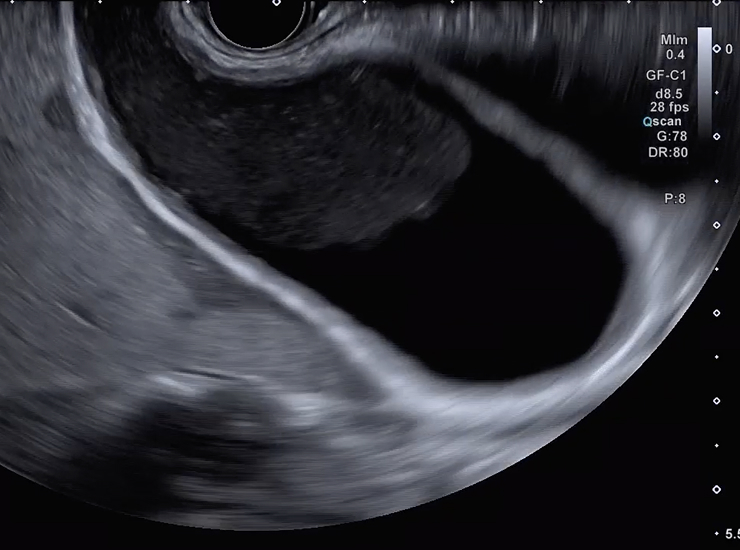

Curved linear array echoendoscope used for therapeutic applications such as tissue sample collection, cyst drainage, biopsies of lesions/lymph nodes and injection for pain management. The GF-UCT180’s ultrasound transducer has a broader bandwidth and higher sensitivity, offering superior ultrasound imaging with high resolution and penetration and less noise when operating in B-mode.4